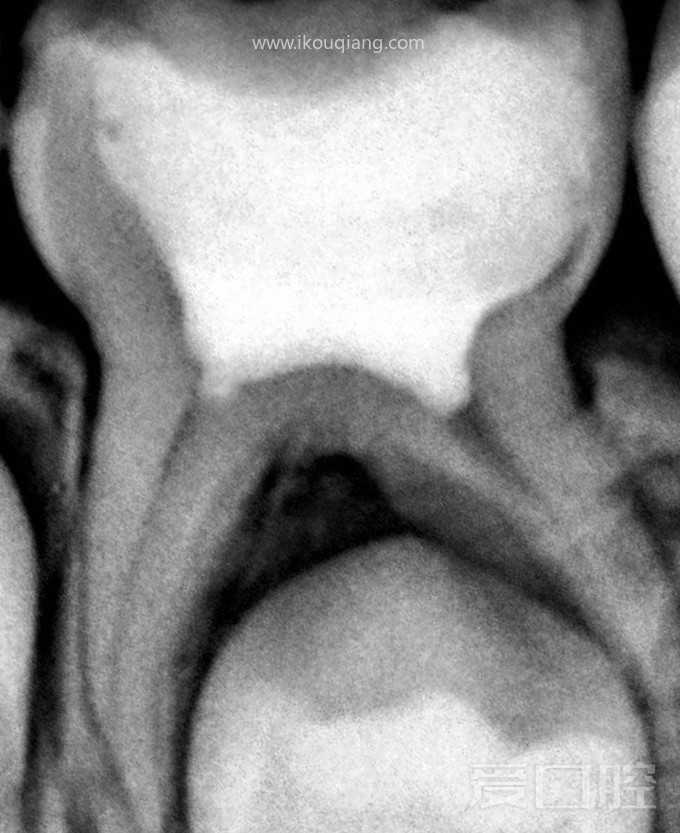

看个乳牙MTA活髓切断术 —— 下颌乳5

by Ahmed Nehme